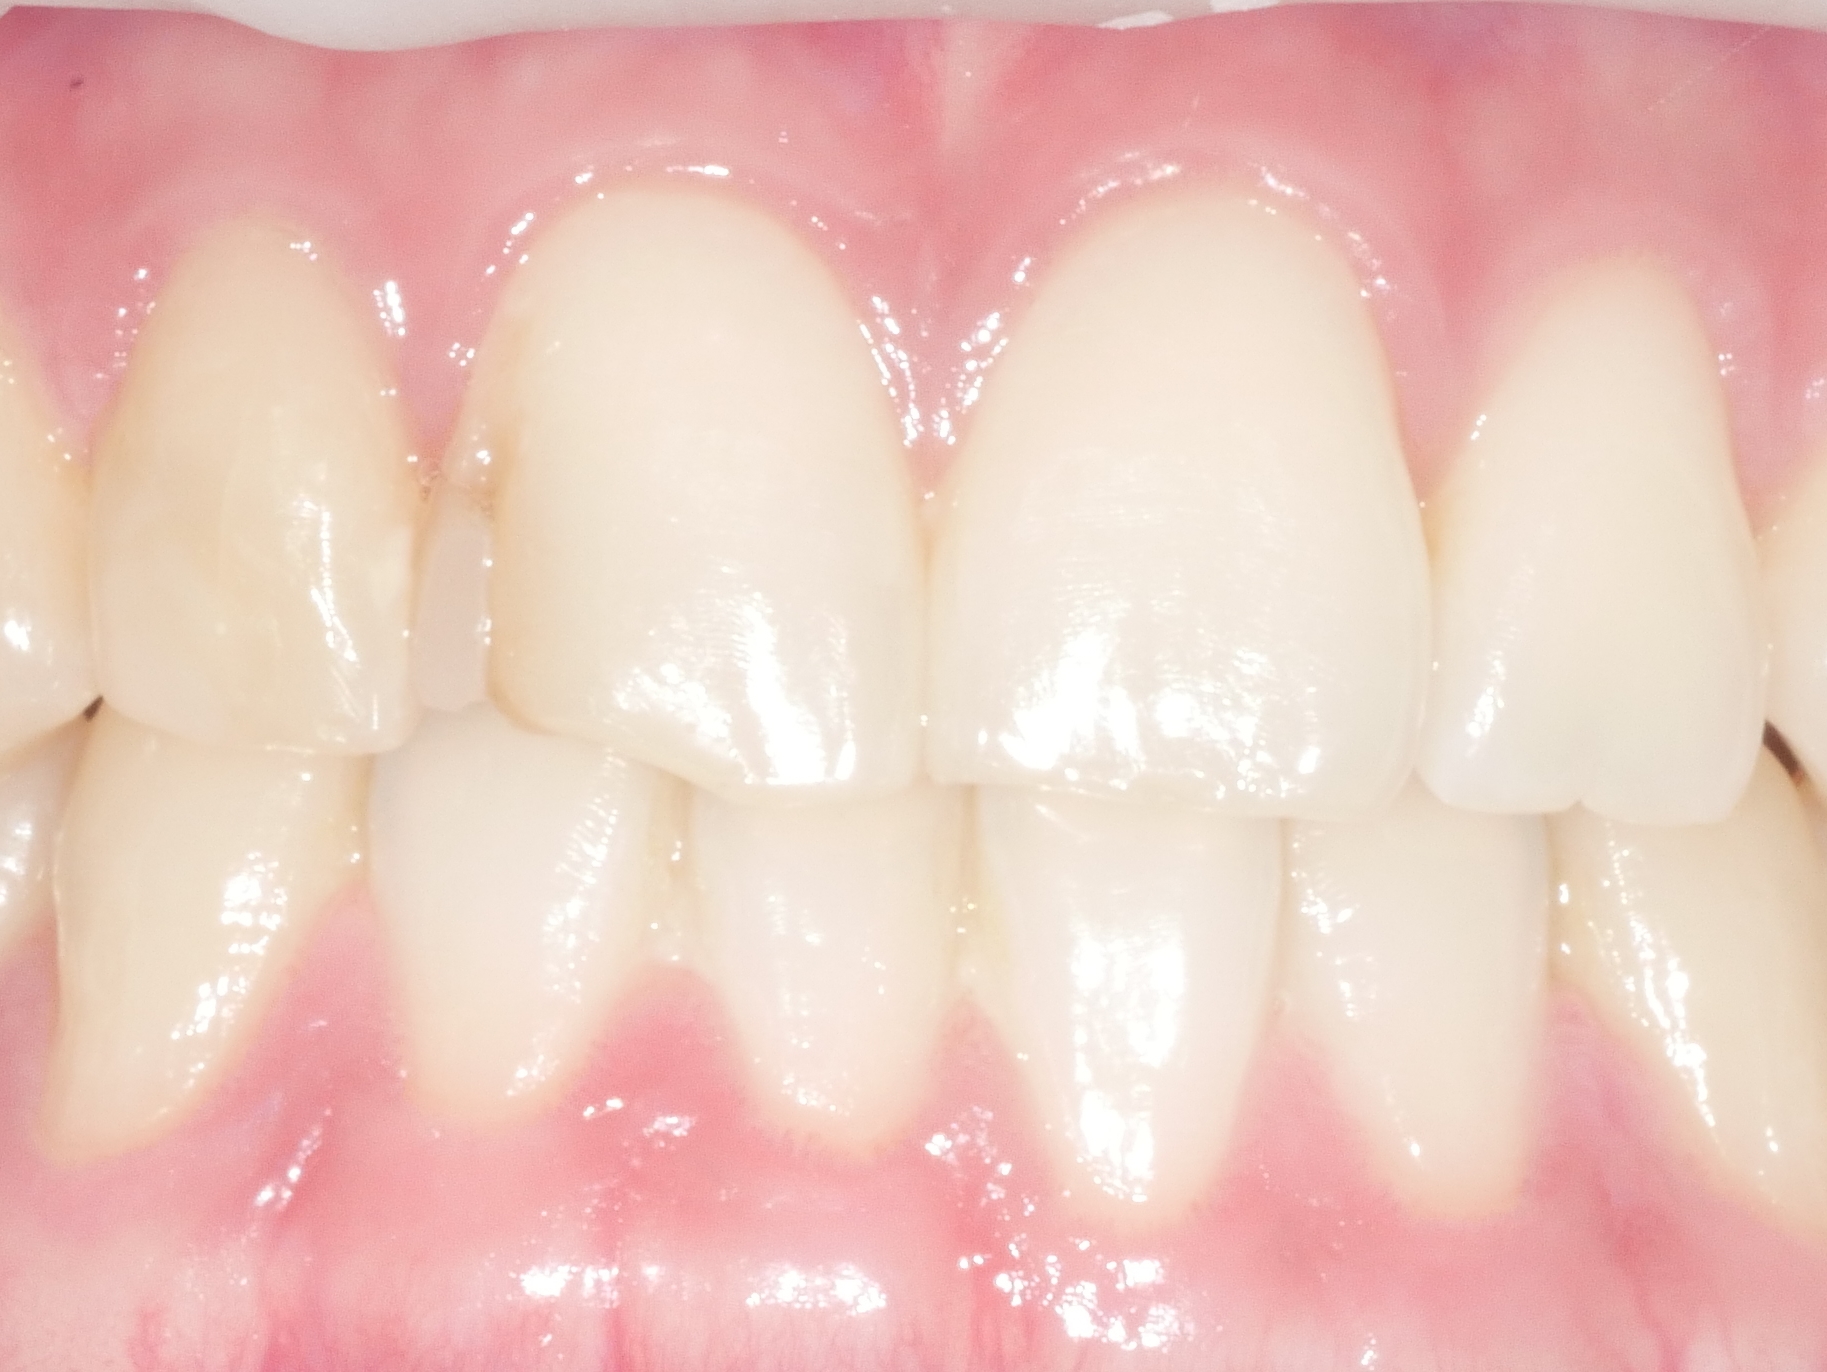

CASE.01 아래 앞니 치아 벌어짐 치료

• 아래 앞니 치아 벌어짐 치료

내원 당일 치아 삭제 없이 레진치료

치료전/후 2024.05.07